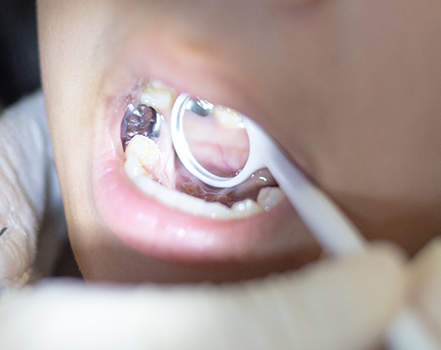

If your child has a permanent tooth and the pulp is infected, we may suggest a root canal. This process involves administering anaesthesia to numb the tooth and its surrounding area before creating a small opening in the crown to access the infected tissue. After clearing out bacteria from the canals and removing the pulp, the tooth will be sealed to prevent future infection. After a few weeks, a customized dental crown can be secured over the tooth so that it can continue to function normally over time.

Pulp therapy is similar to a root canal but is primarily used on baby teeth. Our team will eliminate the pain your child is experiencing by either removing the infected pulp from the chamber in the crown (pulpotomy) or removing all of the pulp tissue from the crown and canals (pulpectomy). We’ll then clean the interior of the tooth and fill it with a biocompatible solution before topping it with a dental crown.